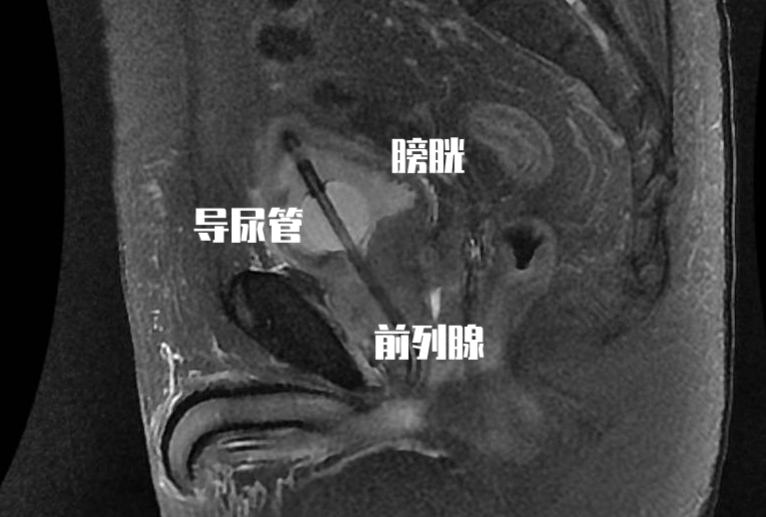

可能讲起来比较难以理解, 我们男性的排尿是当膀胱内充满尿液后会有排尿的冲动信号由膀胱传递至大脑,然后大脑在可以排尿的情况下将信号在传递至膀胱和尿道。这个时候膀胱开始收缩,尿道打开,小便就可以自然排出。而前列腺增生后会带来几种情况,它会刺激我们的膀胱,即使在尿量不充盈的时候也会刺激患者要去排尿,这个时候患者表现出来的就是尿频尿急和夜尿增多,甚至出现尿*禁失**。由于尿道是从前列腺内穿行而出,增生的前列腺腺体又会对尿道产生压迫,这时候就会导致患者的排尿困难。